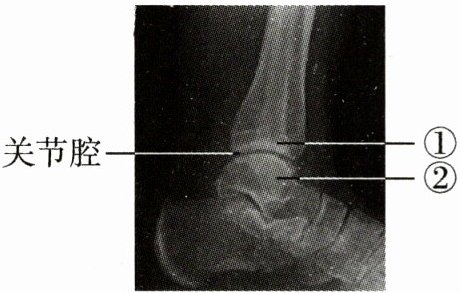

3. 下图为某人的踝关节射线透视图像,①②表示踝关节的组成结构。下列说法错误的是(

A.①是关节头,②是关节窝

B.①②表面覆盖着关节软骨

C.关节腔内有滑液,使关节灵活

D.踝关节在运动中起支点作用

A

A 解析:题图中的①是关节窝,②是关节头;①关节窝、②关节头表面覆盖着关节软骨;关节腔内有滑液,能减少骨与骨之间的摩擦,使关节灵活;运动中,神经系统起调节作用,骨起杠杆作用,关节起支点作用,骨骼肌收缩提供动力,故踝关节在运动中起支点作用。